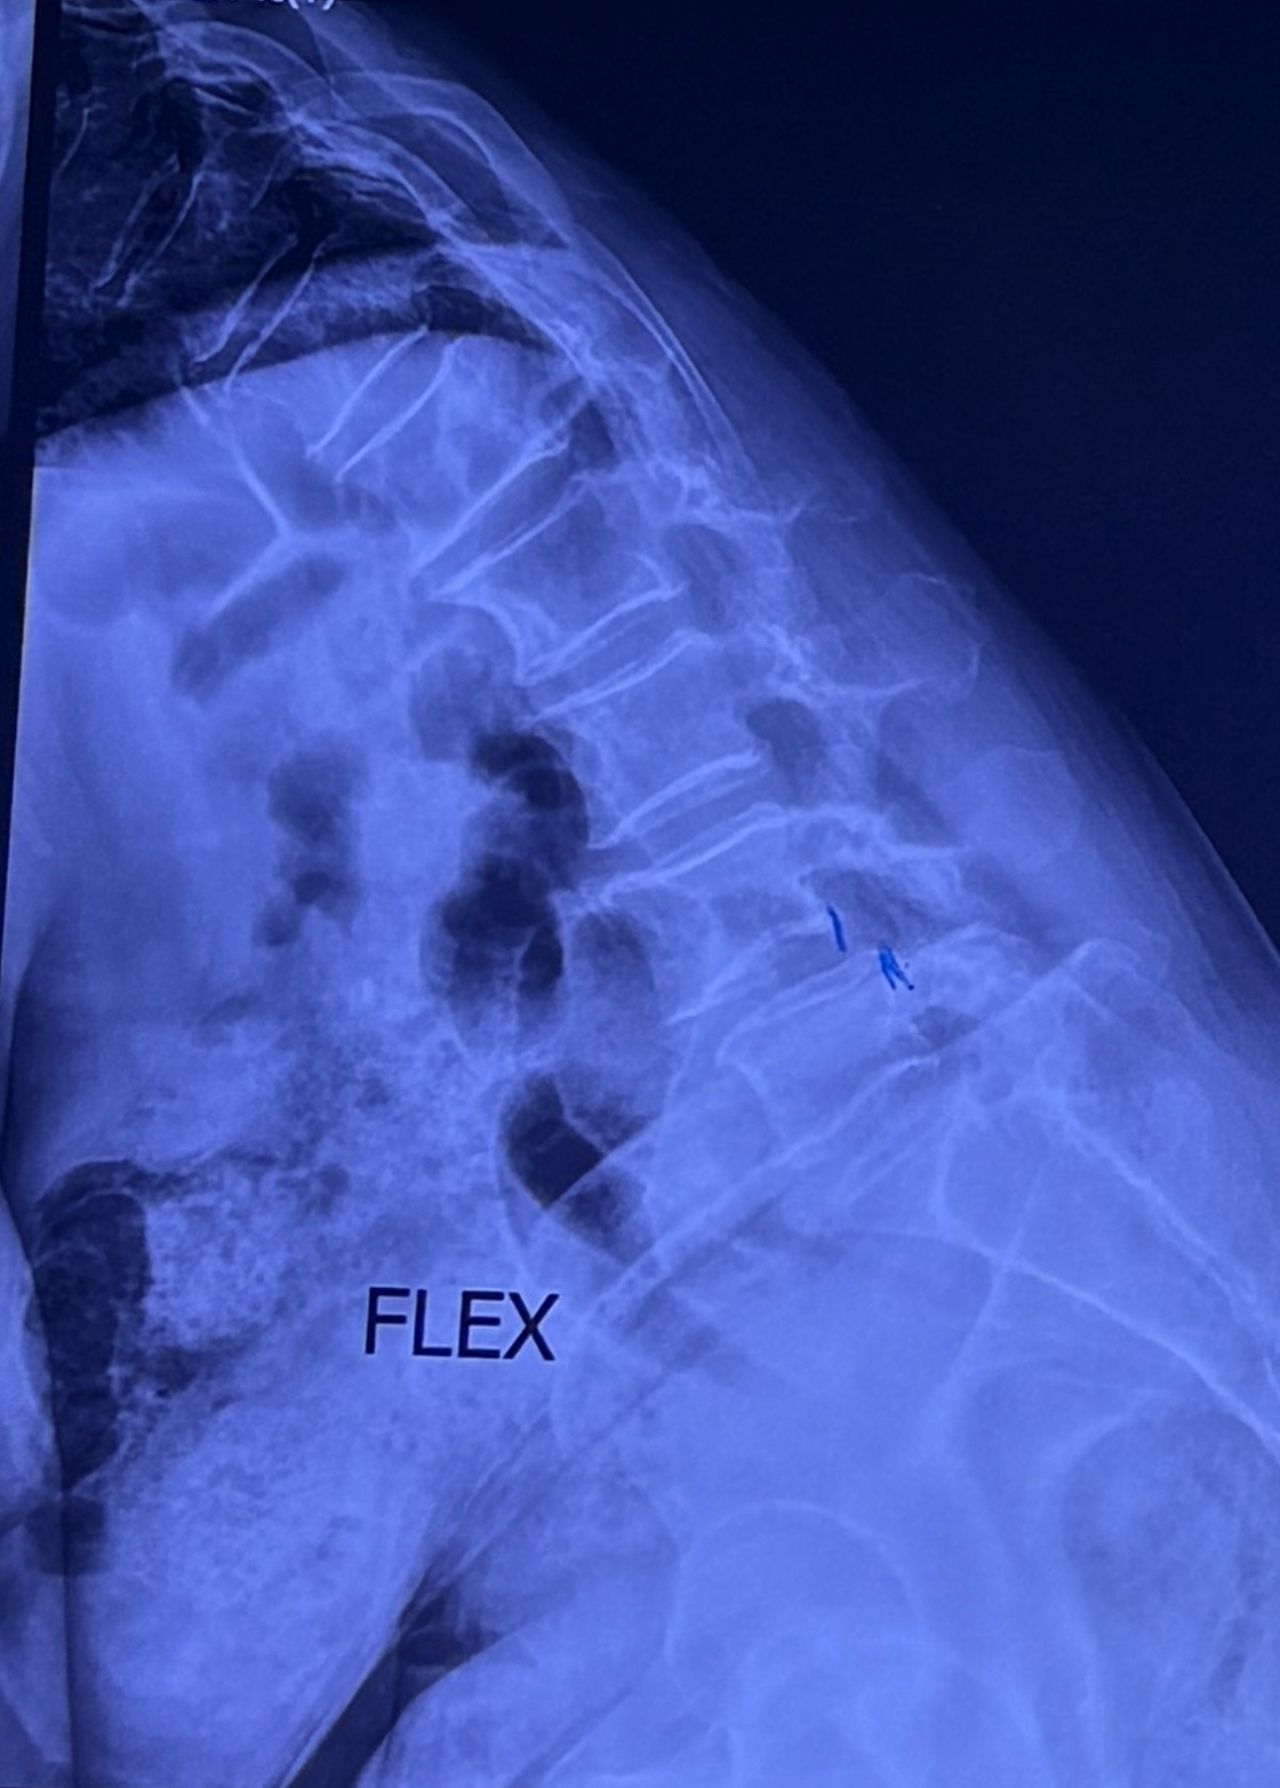

L4-L5 level:

sever L4-5 canal stenosis mainly due to FL hypertrophy?

CSF block. Mild L3 retrolisthesis, facets hypertrophy bilateraly causing L and R IVF stenosis, disc hyperbule

Since I’ve noticed instability in some segments I asked for dynamic L/S x ray:we see mild L4 ant listens due to DjD/DDD. There is not any pars defect.

I will give her treatment via Cox chiropractic flex dis and axial decompression. I would use DTS decompression

Since there is a few mild to moderate DjDs/ DDs in her lower back I won’t use lumbar adjustment on her